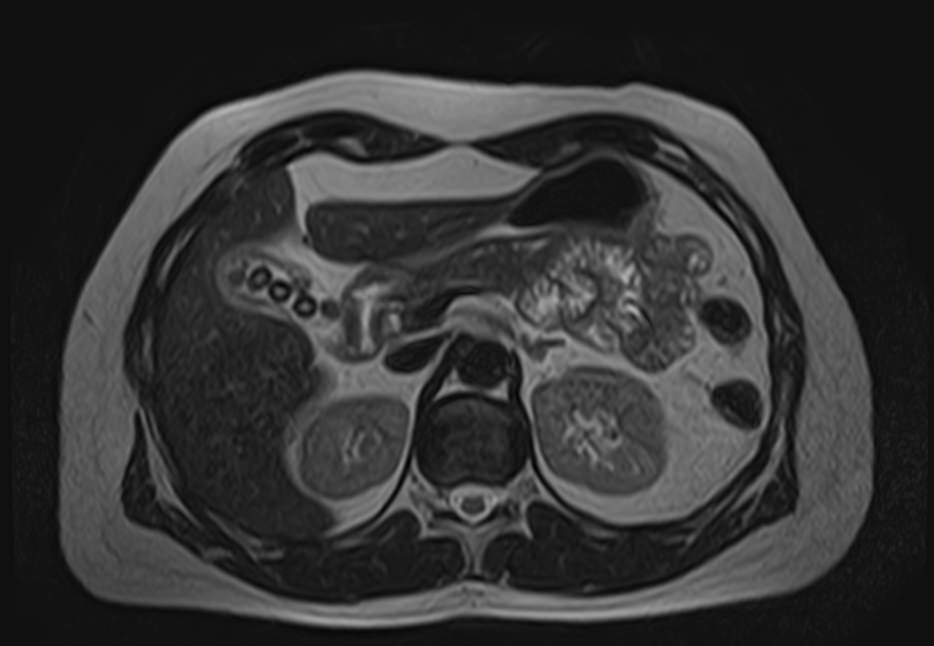

МРТ почек проводится для оценки состояния всех структур этого важнейшего органа выделительной системы, включая паренхиму, чашечки, лоханки почек и сосудистую систему. В клинике «Доступная медицина» исследование выполняется на томографе экспертного уровня TOSHIBA VANTAGE TITAN 1,5 Тесла, который обеспечивает изображения высокой четкости и контрастности, что позволяет проводить точную и достоверную диагностику заболеваний почек.

МРТ используется для диагностики злокачественных и доброкачественных опухолей почек. При этом большую ценность представляет МРТ почек с введением контрастного вещества. Процедура дает возможность не только выявить новообразования, но и установить степень развития патологического процесса, определить распространение метастазов на близлежащие органы. Только МРТ позволяет обнаружить псевдокапсулу новообразования. Такая информация крайне необходима, если речь идет об оперативном лечении рака почки с возможным сохранением органа. Также методика с высокой точностью определяет кистозные образования, распространение метастазов.

МРТ почек показывает:

Исследование используется при лечении различных воспалительных и дегенеративных процессов почек с целью анализа эффективности проведенной терапии. МРТ почек назначается пациентам при наличии противопоказаний к осуществлению рентгенограммы, урографии, в случае неэффективности КТ, ультразвукового сканирования. Дополнительно во время обследования диагност может выявить заболевания мочевыводящих путей, в частности, мочеточников. Показано проведение магнитно-резонансной томографии при эндокринных патологиях (при расстройстве функций надпочечников), злокачественном течении гипертонической болезни. С помощью МРТ почек удается установить травматические повреждения, подтвердить абсцесс органа, мочекаменную болезнь, врожденные аномалии строения.